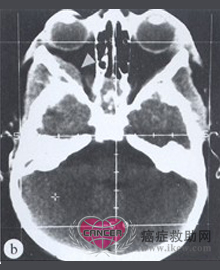

3. CT和磁共振(MRI)检查:可显示肿瘤大小,位置与周围脏器关系,提示能否手术切除。